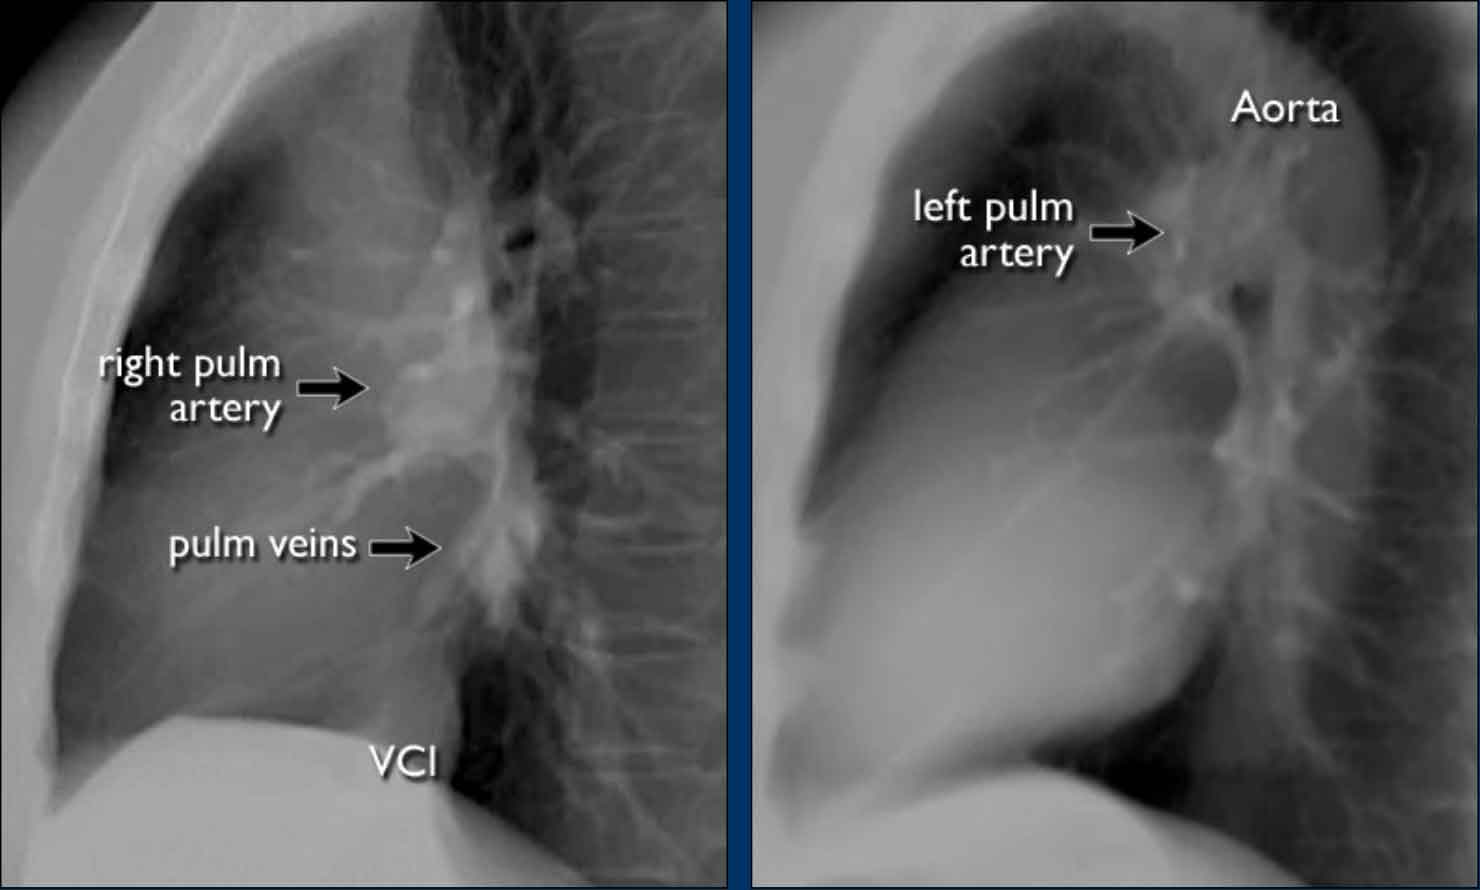

Hili

The normal hilar shadow on chest radiography is predominantly vascular in nature—comprising approximately 99% of pulmonary arteries and, to a lesser extent, pulmonary veins (1).

These vascular structures have well-defined, smooth margins and demonstrate normal branching patterns.

An important anatomical consideration is that the left hilum is normally situated higher than the right.

This relationship arises from the course of the pulmonary arteries: the left pulmonary artery arches over the left main bronchus, while the right pulmonary artery courses anterior to the right main bronchus, which is typically positioned lower than its left counterpart.

In a minority of cases, the hila may be at the same level, but the right hilum should never be higher than the left.

In this illustration, lower lobe pulmonary arteries are colored blue to indicate deoxygenated blood.

These arteries have a more vertical orientation compared to the pulmonary veins, which run more horizontally toward the left atrium, located inferior to the level of the main pulmonary arteries.

On lateral chest radiographs, both pulmonary arteries and veins are identifiable and should not be misinterpreted as lymphadenopathy. Occasionally, pulmonary veins may appear prominent.

The left main pulmonary artery passes superior to the left main bronchus and lies higher than the right pulmonary artery, which courses anterior to the right main bronchus.

The included images are thick-slab sagittal CT reconstructions of the thorax, which enhance visualization of hilar structures.

The lower lobe pulmonary arteries descend from the hilum in a vertically oriented fashion.

Radiographically, these vessels are colloquially referred to as the “little finger” due to their size and shape, approximating that of a little finger (1).

On PA chest radiographs, the "little finger" of the right lower lobe pulmonary artery is visible in approximately 94% of normal individuals, while on the left side it is visible in about 62% (1).